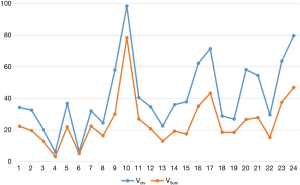

Comparison of Vctv and VSum

As we wanted to evaluate the potential dose advantage of 3D-CT-based versus 4D-CT-based plans, Vctv was created with a 0.5 cm margin from the VC1. The results in Figure 2 show that Vctv has a larger volume than VSum, but the difference varies depending on each patient, which was not the case in the comparison between VC1 and VSum. For the plan based on Vctv and VSum, targets and organs at risk (OARs) endured different doses. The details are shown in next section.

In our study, the average target volume of each phase for the 24 patients was almost half of the VSum, which was approximately equal to the average VC1. The VMip and VExs were nearly equal to VSum. Thus, it appears that not every phase of CT is suitable for target contouring of the breath effect. When using CTMip images for contouring, Muirhead et al. (20) found that this approach was more reliable for I stage non-small cell cancer, while Huang et al. (21) reported that CTMip can improve the target coverage especially for large and irregular target motion. Although a target volume based on CTSum images has the most accuracy, it is also time-consuming; in contrast, CTMip and CTExs images can be adopted to contour the target and keep the accuracy both in volume and dose. For target volumes derived from 3D-CT and 4D-CT, Franks et al. (22) investigated the target coverage for SBRT in these two types CT images, and observed significant decreases in target coverage (V100, 0.84 vs. 0.94). In our work, the comparison of Vctv and VSum showed that Vctv was larger than VSum in every patient, meaning Vctv had a bigger PTV with more dose delivered to the lungs.